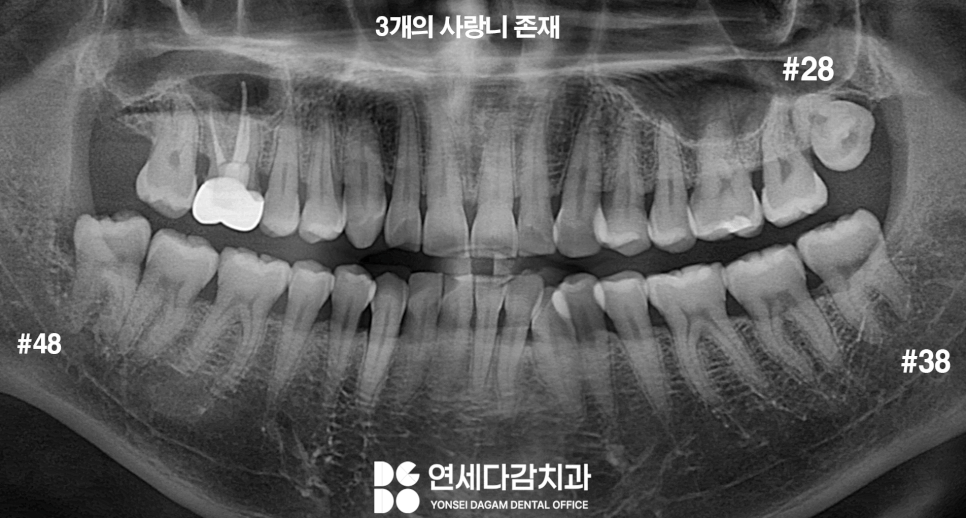

파노라마를 통해 전체적인 위치를

확인했을 때 3개의 사랑니가 있는 것을

볼 수 있습니다.

아래턱에 있는 두 개의 사랑니는

그래도 똑바로 자란 것 같은데,

어째선지 위턱에 하나 있는 사랑니는

방향이 조금 이상하게 보일 겁니다.

아래턱과 다르게 위턱 사랑니의 윗면이

볼 쪽을 향하고 있는 것을 볼 수 있습니다.